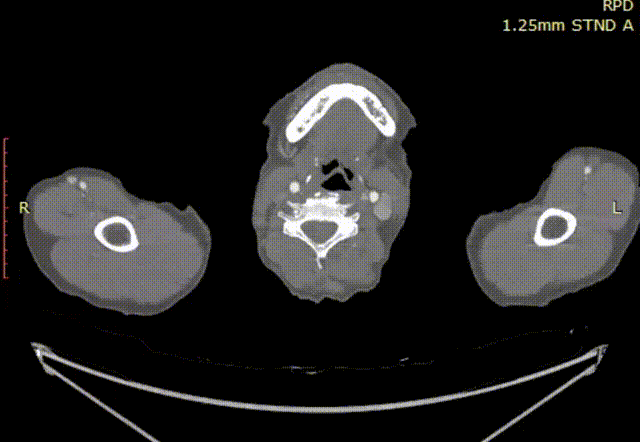

双侧入路直径

手术计划

行右颈动脉-左颈动脉-左锁骨下动脉搭桥术,植入GORE® TAG® 分支型胸主动脉覆膜支架(以下简称“TBE”),TBE主体支架锚定于Zone 0,重建无名动脉血运,左锁骨下动脉栓塞。支架型号:主体支架TAC123715W+分支支架TSB121506W,远端可主动调控胸主动脉覆膜支架TGMR313115。